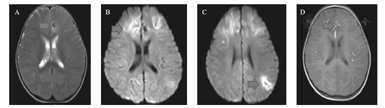

辅助检查:(1)脑电图:入院当日视频脑电图:背景节律减慢(双半球弥漫性2~3 Hz中波幅δ活动为主,夹杂4~6 Hz中波幅θ活动),弥漫性慢波,双额、左颞区尖波、尖慢波、多形性慢波周期性发放,左额为著,清醒期左顶尖波散发,监测到数次临床及临床下电发作。出院时动态脑电图:异常幼儿脑电图(背景活动为弥漫性δ波,睡眠期右侧中央、顶区、左侧顶区棘慢波、尖慢波非同步发放)。(2)头部影像学:入院当天头CT提示颅内出血(图1)。第2天头部MRI符合出血性脑炎表现(图2)。第17天头MRI示双侧额叶、左颞、顶叶弥漫病变,脑炎恢复期改变,左脑额叶脑出血范围较前缩小。弥散成像未见确切异常(图3)。(3)其他:双耳客观听阈检查正常,脑干听觉诱发电位正常,肝胆脾超声正常,双眼闪光视觉诱发电位正常。

A、B:双侧额叶及左侧颞、顶叶见多发斑片状长T1长T2信号,左侧额叶见小斑片状高T1低T2信号影。C、D:DWI图示脑内病变为弥散受限高信号影,表观弥散系数图见低信号征象。